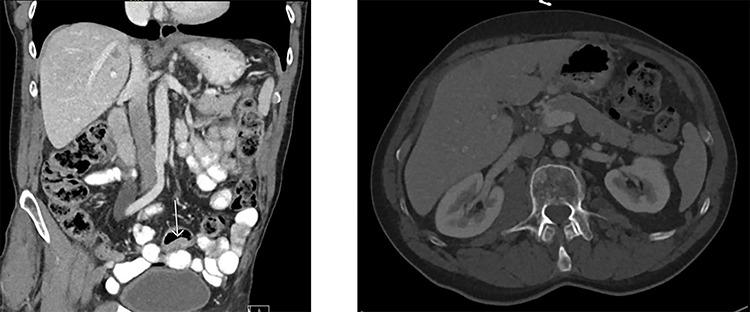

Metastases of colorectal carcinoma (CRC) in the testis are very rare and indicate an advanced stage of disease. In this case report, we present a patient with adenocarcinoma in the sigmoid colon with metastasis in the right testis. Testicular metastasis of CRC is mostly diagnosed late because of their low incidence rate. Patients with CRC and testicular metastasis have a poor prognosis. In this case, the patient turned out to have peritoneal metastasis and one should be aware that testicular metastasis could be the first sign of widespread disease.

结直肠癌(CRC)转移至睾丸非常罕见,提示疾病已处于晚期。在本病例报告中,我们呈现了一名患有乙状结肠癌并伴有右侧睾丸转移的患者。由于结直肠癌睾丸转移的发生率较低,其大多在晚期才被诊断出来。患有结直肠癌并伴有睾丸转移的患者预后较差。在本病例中,该患者最终被发现有腹膜转移,应意识到睾丸转移可能是广泛疾病的首个迹象。